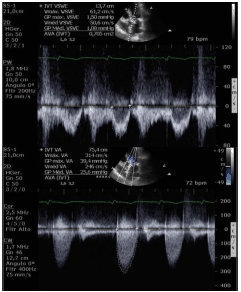

Considerando uma paciente de 87 anos, portadora de hipertensão arterial sistêmica, admitida com dor torácica e dispneia aos pequenos esforços. Ao exame: PA = 110 x 80 mmHg e FC = 72 bpm, nota-se sopro sistólico em foco aórtico 3+/6+, mesosistólico e A2 reduzido. ECG com ritmo de FA e sobrecarga ventricular esquerda. Ecocardiograma com cúspides espessadas e restrição na abertura.

Analise as imagens e dados abaixo:

- Superfície corporal = 1,9 m2;

- FE 2D = 56%;

- Septo = 14 mm;

- Parede posterior = 13 mm;

- PSAP = 40 mmHg;

- Volume AE = 54 ml/m2;

- VSVE = 2,2 cm;

- IM moderada e IAo leve;

- Gradiente VE/Ao máximo = 39 mmHg e médio = 25 mmHg;

- VTI VSVE = 13 cm, VTI AO = 75 cm.

Com base nesses dados e imagens, é correto afirmar que trata-se de estenose